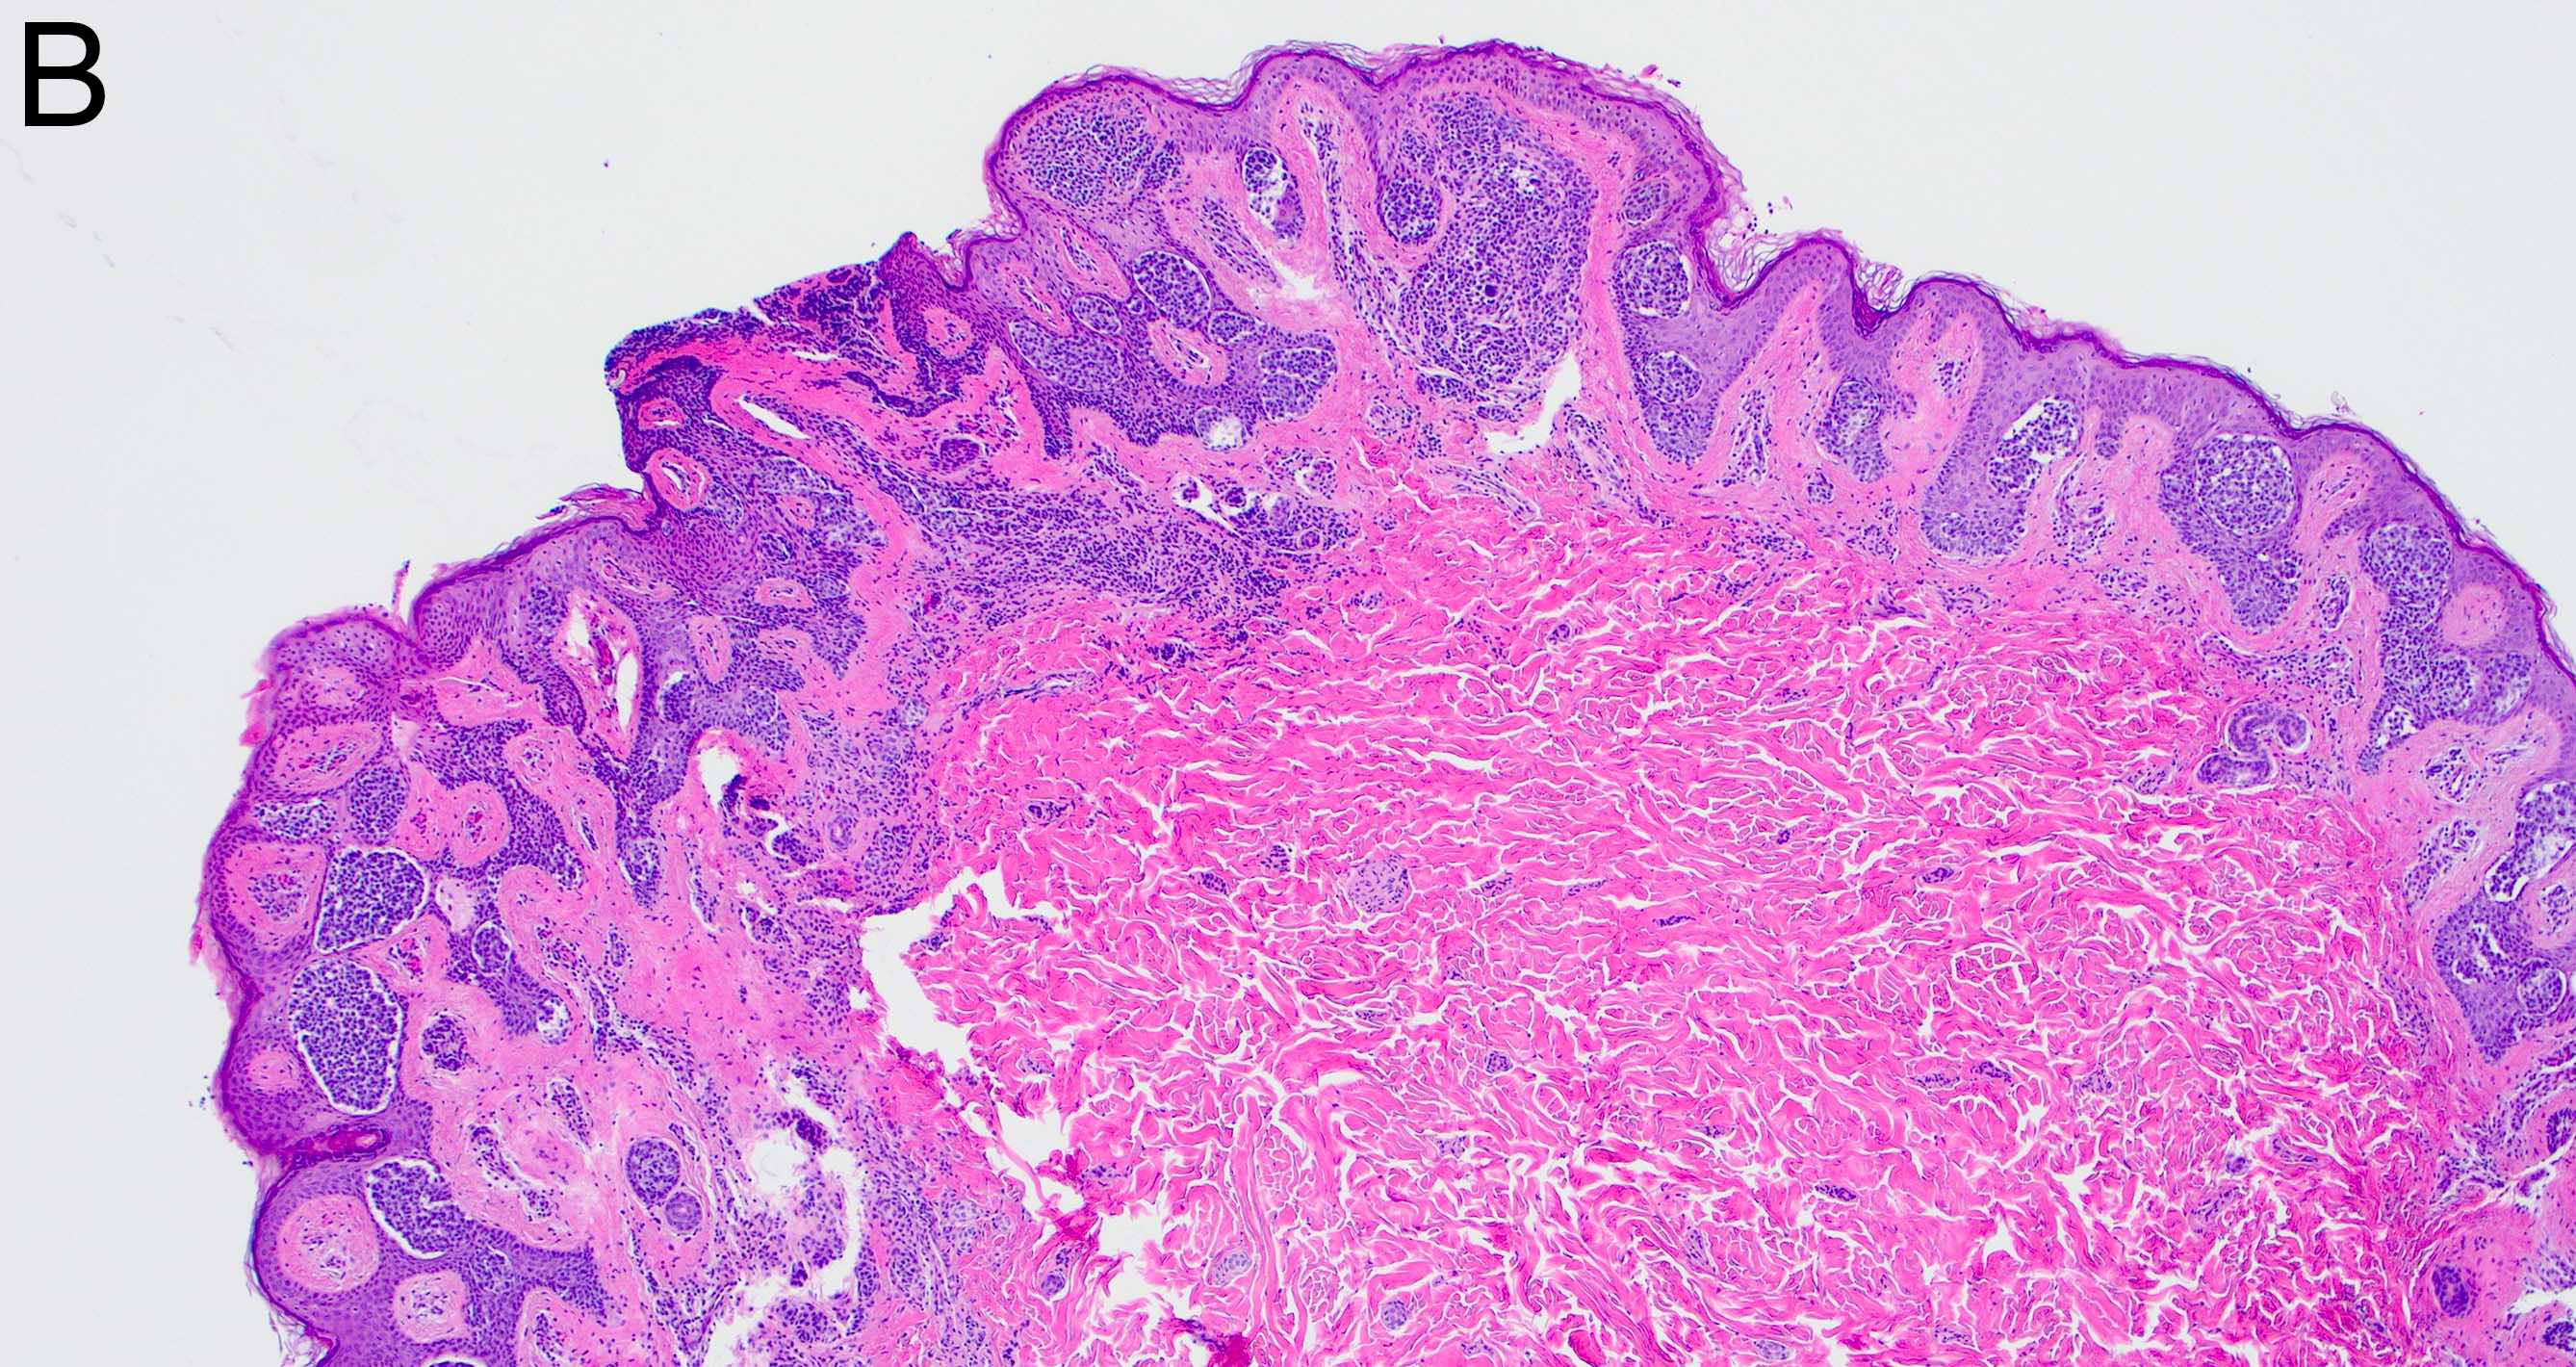

- Melanocytic nevi of the genitals (Am J Surg Pathol 2008;32:51):

- May contain large dyshesive irregular nests in close proximity to one another

- May contain a prominent lentiginous component

- Deeper nests may evoke a stromal fibrotic host response

- Lesion should maintain symmetry, circumscription and maturation

- Pagetoid growth can be seen but typically does not extend into granular layer

- Junctional component may extend into adnexal structures

- Significant cytologic atypia can occur

- Melanocytic nevi of the breast (Am J Dermatopathol 2016;38:867):

- May contain large irregular dyshesive nests in close proximity to one another

- Junctional nests may not be centered and can be placed within inter-rete spaces and along sides of rete

- Nests may have variable pigmentation (results in globules seen on dermoscopic exam)

- Nests may have prominent horizontal streaming resulting in rete blunting or epidermal effacement

- Cytologic atypia is common

- Maturation with melanocyte descent should be retained

Microscopic (histologic) images